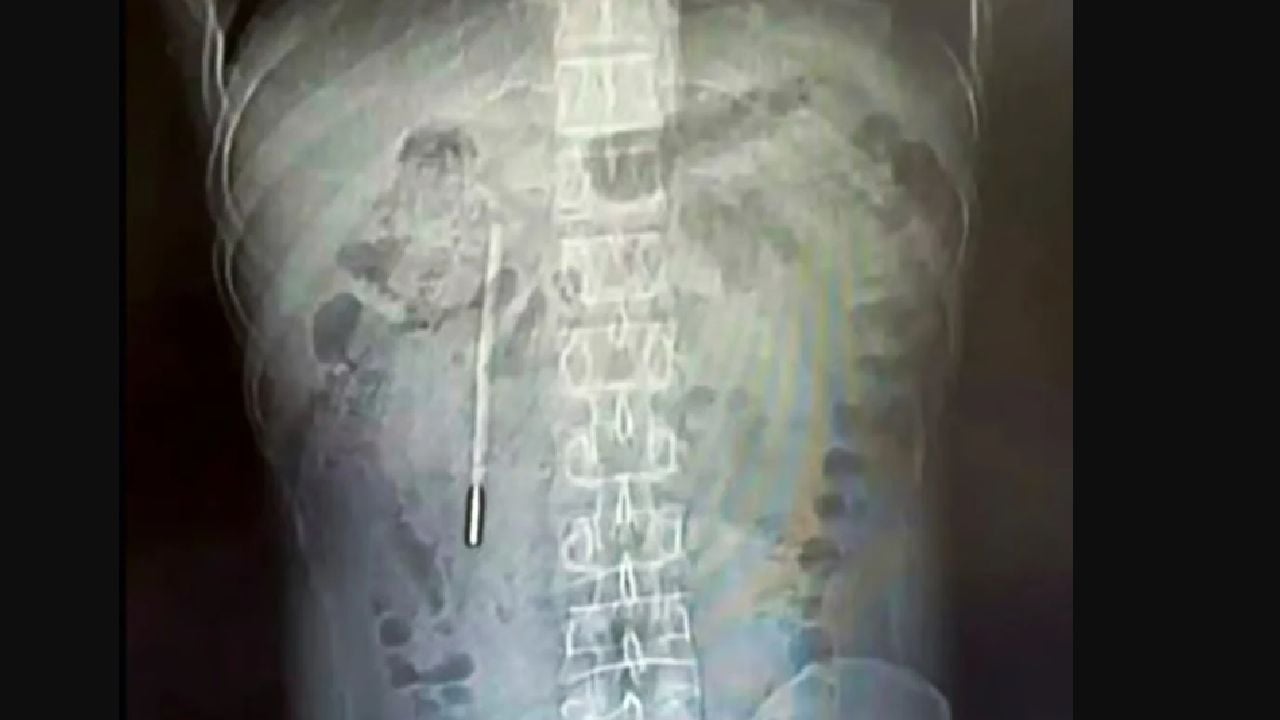

Wang a ajuns la filiala Longgang a Spitalului Universitar de Medicină Wenzhou, unde medicii au realizat o scanare abdominală. Aceasta a relevat prezența unui obiect străin în duodenul său, un aspect care nu era evident pe baza simptomelor sale inițiale. Radiografiile ulterioare au confirmat prezența termometrului, acesta fiind poziționat periculos aproape de peretele intestinal, ceea ce putea duce la perforații severe și hemoragii interne.

Acest caz subliniază importanța diagnosticării corecte în cazurile de dureri abdominale inexplicabile. Medicii au fost nevoiți să acționeze rapid, având în vedere riscurile asociate cu prezența unui obiect străin în organism. Wang a recunoscut că a înghițit termometrul din greșeală la vârsta de 12 ani, dar nu a avut curajul să le spună părinților săi, din teamă că va fi pedepsit. Această omisiune a fost extrem de riscantă, având în vedere că perioada de timp în care obiectul a stat în organism a fost de două decenii.

După ce medicii au confirmat prezența termometrului, Wang a fost supus unei intervenții chirurgicale de urgență. Procedura a fost una riscantă, dat fiind că obiectul era poziționat aproape de peretele intestinal. Medicii au reușit să extragă termometrul intact, deși marcajele de pe acesta erau complet șterse, ceea ce sugerează că obiectul a fost expus acidului gastric timp de mulți ani. Această intervenție nu a fost doar o chestiune de urgență, ci a fost și o lecție despre importanța îngrijirii sănătății digestive.